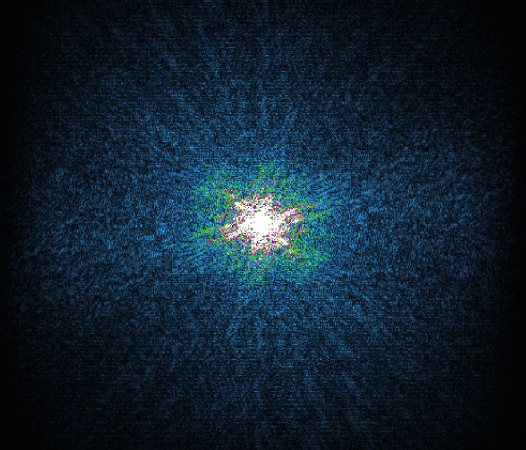

In the example below, only one fifth of the required MR radiofrequency signals is recorded. This results in a five times faster acquisition, with a subsampled k-space (top left) and inherent image artifacts after standard reconstruction (top right).

Basic compressed sensing principle

K space

K-space compressed sense

The Compressed SENSE reconstruction then uses iterative, knowledge-based algorithms to fill in the empty lines in k-space (bottom left). This removes the artifacts while keeping the final image fully consistent with the acquired data (bottom right).